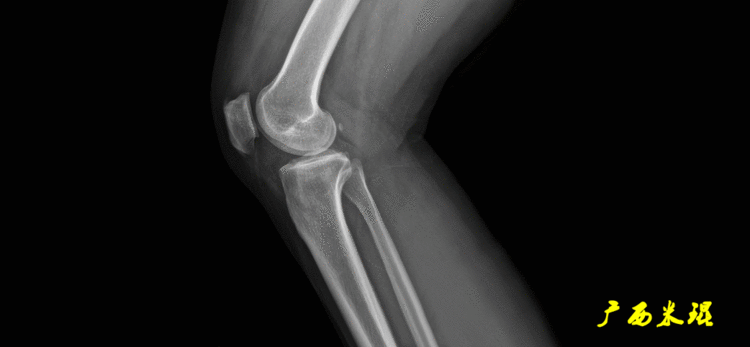

(2)膝关节中心膝关节中心点常用的有5个不同的定位方法,分别是股骨髁中点、股骨髁间窝顶点、膝关节间隙水平软组织中点、胫骨髁间嵴中点和胫骨平台中点,我们可以根据具体情况来选用。

2、画出下肢的轴线确定髋关节、膝关节、踝关节的中心点后,我们才能了解下肢的几个轴线。(1)解剖轴股骨和胫骨的骨干中线为解剖轴,股骨解剖轴和胫骨解剖轴的夹角正常值为174°±1°。

股骨远端外侧角(mLDFA):股骨内外侧髁远端切线(关节线)与股骨头和膝关节中心的连线(机械轴)两者之间形成的外侧夹角,正常为87°±3°。

5、画出与解剖轴相关的角度解剖股胫角(aFTA):股骨干下段轴线(解剖轴)与胫骨上段轴线(解剖轴)在膝关节所形成的夹角,正常为174°±1°。膝关节OA的畸形常常由于一侧软组织及关节的过度磨损所致,临床多为内侧磨损过度,因此表现为轻度膝内翻畸形,X线表现为解剖股胫角小于174°,而胫骨角正常。

解剖股骨远端外侧角(aLDFA):股骨干下段轴线(解剖轴)与股骨内外侧髁远端切线(关节线)在膝关节外侧所形成的夹角,正常为81°±2°。大多数膝外翻患者的畸形发生于股骨下端,表现为股骨远端外侧角小于正常值。